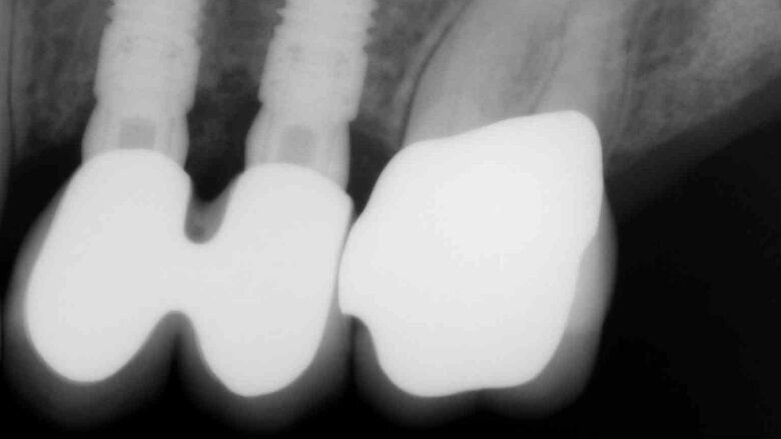

Fig. 6c_Controllo rx a 2 anni dal posizionamento implantare.

Fig. 7_Primo caso eseguito nel 2011, rx di controllo a 3 anni dal posizionamento implantare.